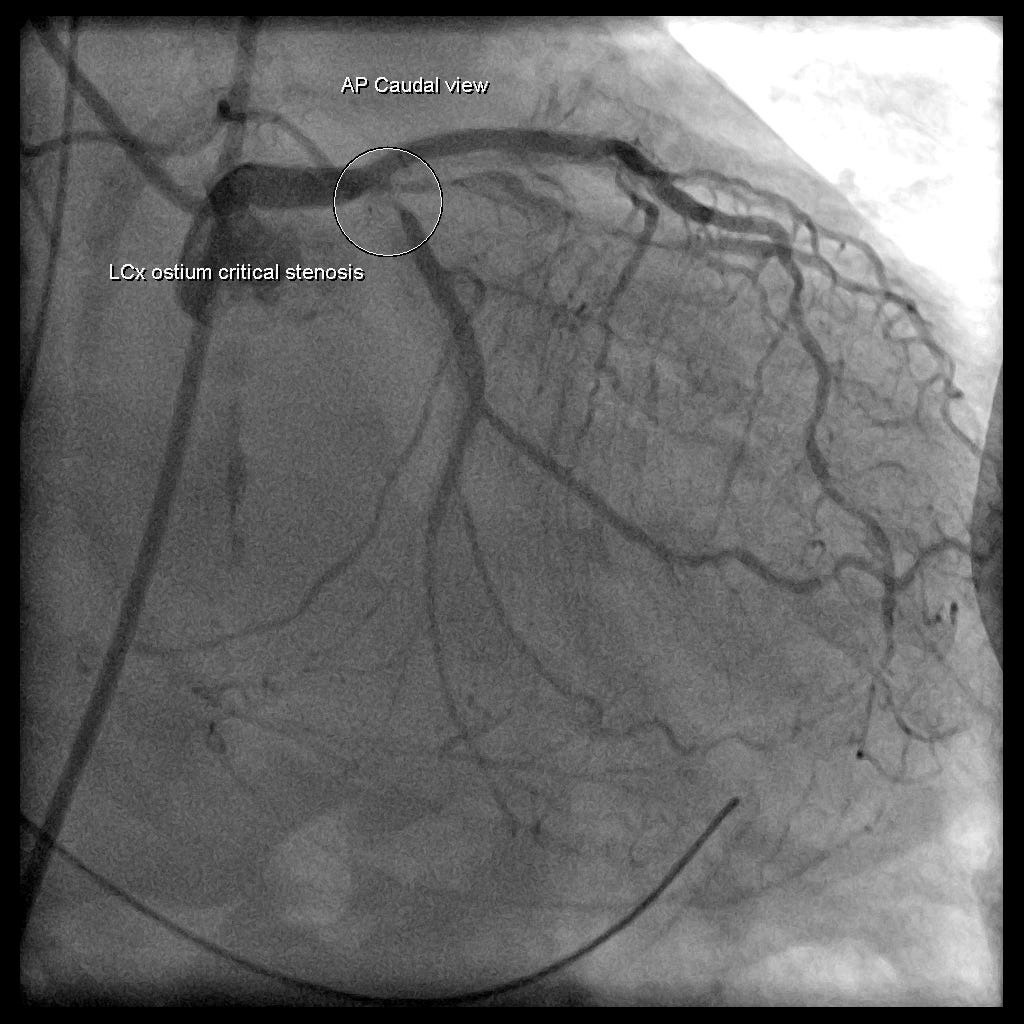

病患4小時後的TnI飆到250 ng/ml(Large myocardial infarction)。之後在5小時後進入導管室去做PCI。CAG如下Fig.5,顯示了LCx critical stenosis與RCA CTO

所以這個Case是因為LCx critical stenosis引起的large myocardial infarction導致collapse,並不是因為肺栓塞引起。